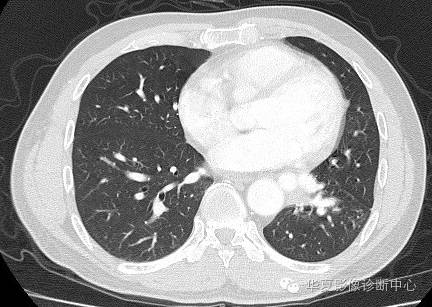

| 影像表现及分析: | 影像表现:定位左下叶;左下叶体积缩小,整体密度增高,支气管分布正常,其内见血管增多,但是走形正常,未见杂乱、迂曲的血管影;血管连向肺门下方软组织密度结节灶,结节与主动脉分界不清,增强后,见降主动脉发出异常粗大血管供血整个左下叶,左下肺动脉细小。 |

异常体动脉供应正常下肺基底段完整含义为起源于降主动脉的异常动脉供应下肺基底段,而基底段支气管树和肺实质正常,同时基底段肺动脉缺如或狭窄【大部分缺如(完全型),部分狭窄(不完全型)】;95%以上累及左下肺,因此也称为异常体动脉供应正常左下肺基底段。 病因尚未明确,可能是胚胎发育时期供应肺芽的背主动脉原始小分支退化不全,与肺实质形成异常连接,并影响肺动脉与肺血管床连接而导致此部位肺动脉发育不良,而支气管、肺组织的发育未受影响。本病的病理生理基础为左向左的分流,体动脉供应的肺组织充血,体循环的高压可增加肺血管床的压力和左心负荷,同时也增加肺循环量和压力而增加右心负荷,导致各种临床症群。本病可无临床症状,部分患者可有咯血、呼吸道感染、呼吸困难、充血性心力衰竭。 影像表现:左肺下叶体积缩小,整体密度稍增高,支气管树走形、分布正常,血管增多、稍增粗;增强后显示左下肺动脉幼小,甚至不发育;下叶由主动脉发出的粗大血管供血。 |